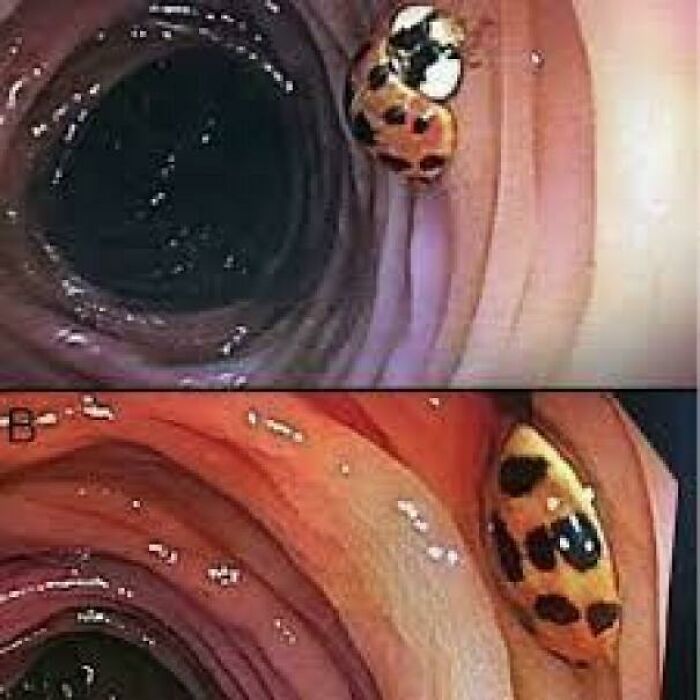

When a Colonoscopy Finds a Very Unwanted Visitor